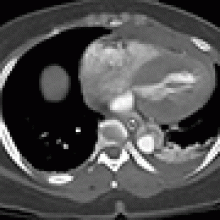

A 49-year-old woman with a history of hypertension and smoking presented to an outside hospital with sudden onset chest pain and hypotension. Computed Tomography/ Angiography (CTA) of the chest and abdomen revealed a type A aortic dissection extending from the ascending aorta to the left common iliac artery. (Figure 1) Of note, there was a significant pericardial effusion and left pleural effusion. Due to her hypotension and tamponade physiology, the patient was rapidly intubated followed by unsuccessful pericardiocentesis. The patient was then transferred to our institution for emergent dissection repair.

Figure 1a-e. Computed Tomography/Angiography (CTA) at

presentation demonstrating a type A aortic dissection.

[3]Figure 1a. Axial CT at level of the pulmonary artery. The false lumen in the ascending aorta (white arrow) has minimal flow.